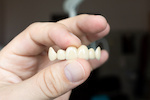

保険適用の白い詰め物には、主に「コンポジットレジン(プラスチック)」があります。これらは、見た目が自然で、歯にフィットするため、美容的な利点が高いです。

- プラスチック素材で作られた詰め物

- 前歯の治療に使われることが多い

- セラミックよりも強度は劣るが、価格は安価